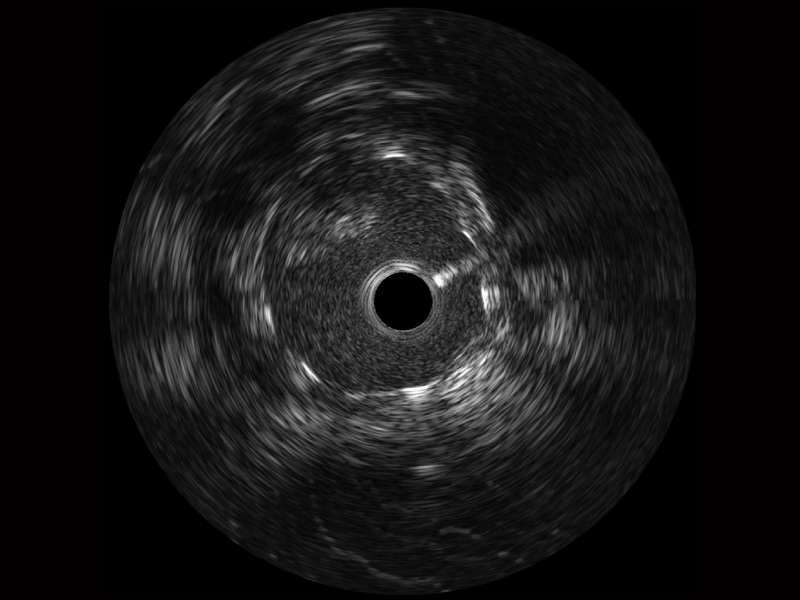

开立宽频IVUS图像

对比传统IVUS导管成像,开立宽频IVUS图像的近场支架梁显影更细腻,远场中膜外血管仍清晰可辨,兼顾远中近,兼顾分辨力与穿透深度